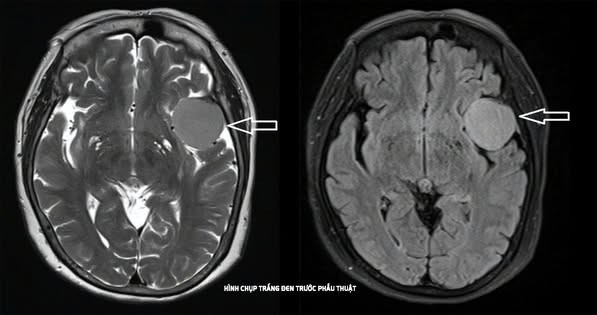

Bệnh nhân P.T.N, 73 tuổi, ngụ tại phường Tam Bình, TP HCM, được phát hiện khối u màng não thái dương trái kích thước 3,5x5cm sau khi đi khám vì triệu chứng đau đầu kéo dài.

Trước đó, bệnh nhân chỉ có biểu hiện đau đầu nhẹ và được điều trị giảm đau thông thường không hiệu quả. Đến khi bị té ngã trong lúc tắm, gia đình đưa bà đến Bệnh viện Đa khoa Thủ Đức thăm khám. Qua chụp CT và MRI, các bác sĩ phát hiện khối u màng não đáng ngại, vị trí sàn sọ phức tạp cần can thiệp phẫu thuật.

Hình ảnh khối u trên phim chụp - Ảnh BVCC